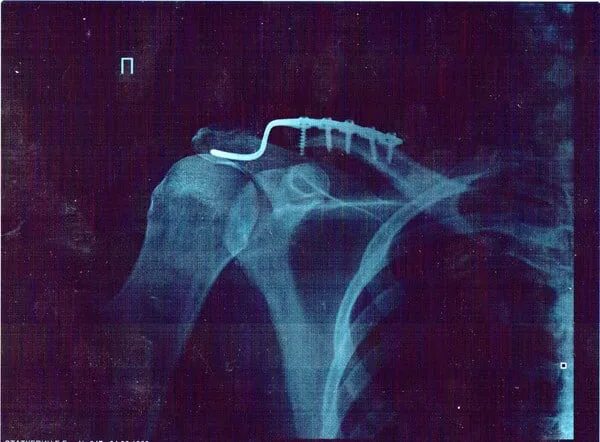

После разрыва акс. После разрыва акс. Разрыв акс остеосинтез крючковидной пластиной. Травматический акромиального конца ключицы вывих плеча. Акромиальный отросток ключицы перелом.

Перелом ключицы остеосинтез. Акромиально-ключичный сустав рентген. Разрыв акс остеосинтез крючковидной пластиной. Вывих грудино ключичного сустава рентген. Вывих акромиального конца рентген.

Остеосинтез акромиально-ключичного сочленения. Разрыв акромиально-ключичного сочленения. Остеосинтез акс крючковидной пластиной. После разрыва акс. Перелом акромиального конца ключицы остеосинтез.

Разрыв акромиально-ключичного сочленения рентген. Разрыв акс остеосинтез крючковидной пластиной. Вывих акромиального конца рентген. Разрыв акс плечевого сустава степени. Остеосинтез акромиально-ключичного сочленения рентген.